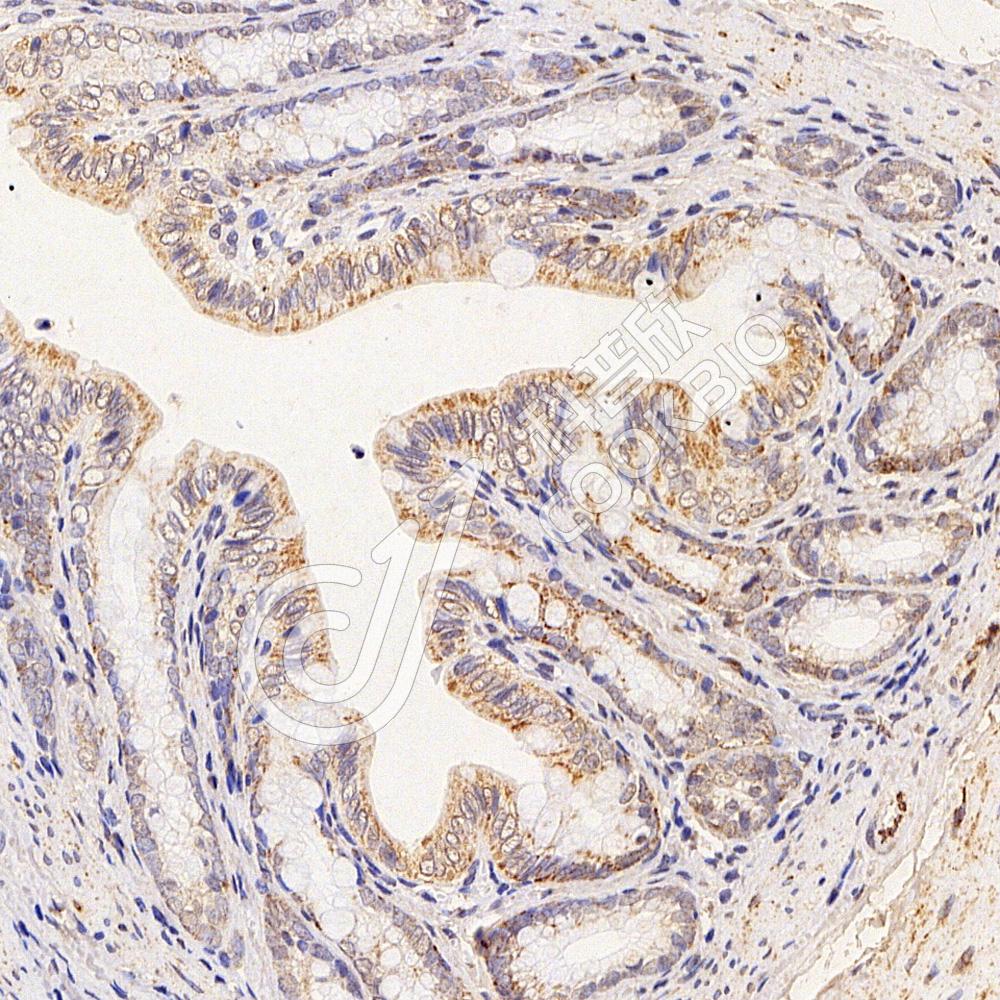

IHC检测TMEM177蛋白(货号 K1340029).

样品: 小鼠结肠, 4%多聚甲醛 (货号KSG1101) 固定12-24小时.

抗原修复: 柠檬酸抗原修复液(干粉, pH 6.0) (KSG1201), 98℃, 20分钟.

—抗: 1: 800稀释, 4℃ 孵育过夜.

二抗: S-vision免疫组化多聚二抗(山羊抗兔),即用型 (货号KB3906), 室温孵育20分钟.

样品: 大鼠结肠, 4%多聚甲醛 (货号KSG1101) 固定12-24小时.